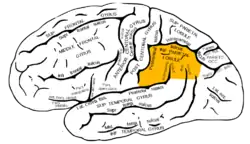

Lateral surface of left cerebral hemisphere, viewed from the side. (Inferior parietal lobule is shown in orange.) | |

.png.webp) Superficial anatomy of the inferior parietal lobule.